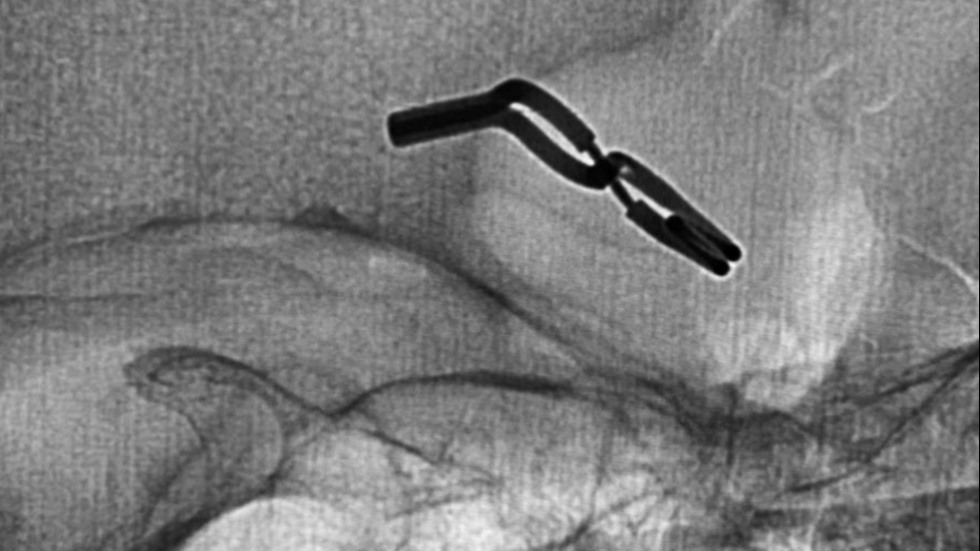

Surgical Clip